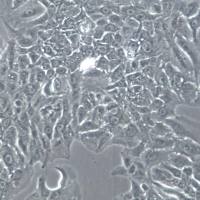

HUVEC

,抑制这一过程将能明显阻止肿瘤组织的发展和扩散转移。 血管生成实验的技术原理主要是应用Matrigel模拟机体环境,上面接种肿瘤细胞,观察血管生成情况。体外的血管生成实验能很好的模拟肿瘤的血管发生过程,并且适合研究药物对这一过程的影响实验。我们以HUVEC细胞为例,介绍这一实验的详细过程。 一、实验材料 二、实验方法 1、主要步骤Step1:细胞培养Step2:细胞转染或药物处理Step3:铺Matrigel胶Step4:接种细胞Step5:观察血管生成情况 实验过程中需要注意

【求助】使用VEGF刺激HUVEC检测VEGFR2磷酸化,需要饥饿细胞吗?

青鸟使者 小弟最近在研究VEGFR2的一个小分子抑制剂,请问高手,使用20ng/ml 的VEGF刺激HUVEC细胞前需要去血清饥饿细胞吗?如果需要,要饥饿多长时间? 青鸟使者 求助啊,有人知道吗? snowwinds 我们养的是肺上皮细胞。一般是无血清培养24h后加刺激因素。 lij_try 青鸟使者,你好,我一直找不到HUVEC细胞,请问您能否送我一株